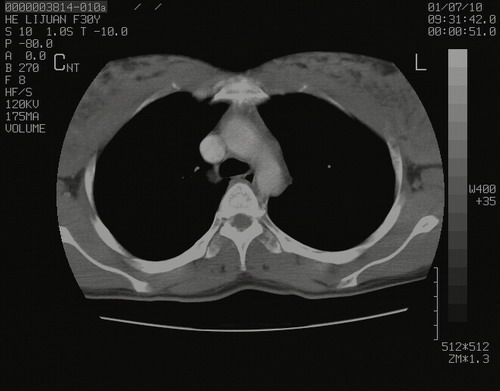

怀孕3个月时(2009-3至4月间),自述突感左侧前后胸疼痛1天,以前胸明显,随后偶感闷痛,余未见异

左肺尖脊柱旁沟肿块,境界清楚,边缘光滑,密度不均,内有多发点片状钙化,考虑良性肿瘤,骨软骨瘤或神经源性肿瘤可能,肺错构瘤不除外。

左后上纵隔见一类圆形肿块影,外侧边界清,密度不均匀,内可见点状钙化影,增强呈不均匀强化,考虑神经源性肿瘤可能。期待病理结果。